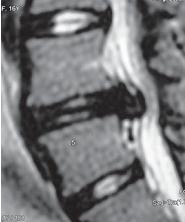

МРТ № 97

На МРТ № 97 у шестнадцатилетней пациентки наблюдается секвестрированная грыжа межпозвонкового диска в сегменте LIV-LV.